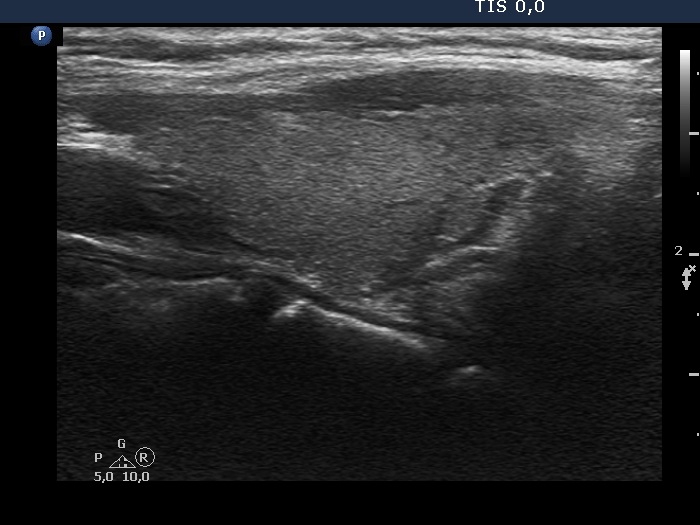

TIRADS - case 2143 (ultrasonographic picture 6)

Left lobe, longitudinal view.